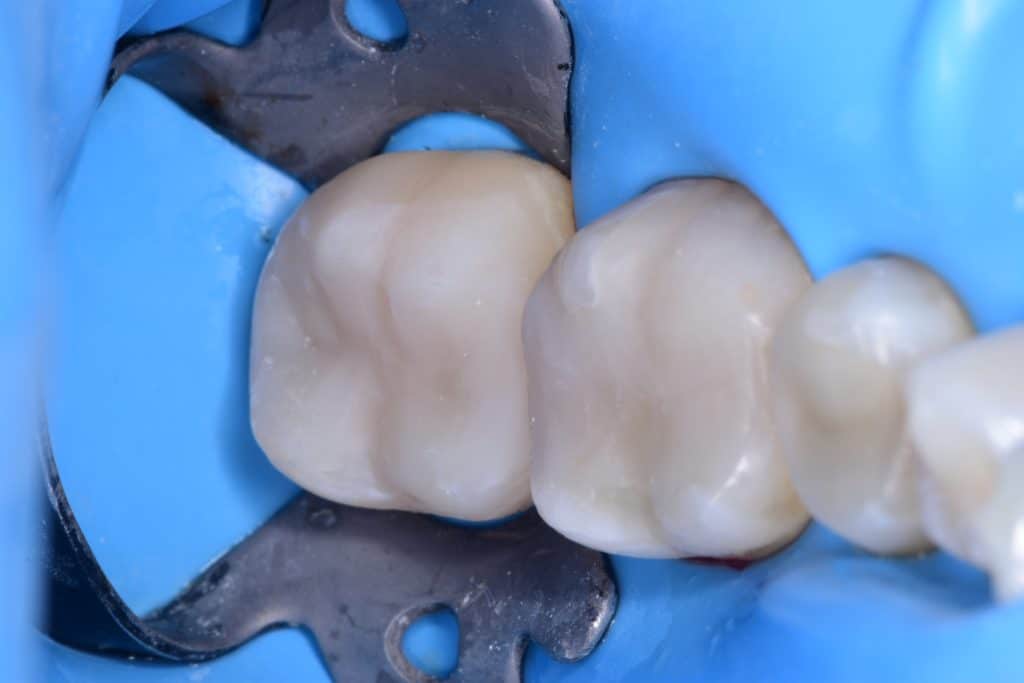

Immediate result

Direct view

Final result

Look to the fitness of the restoration on the tooth surface